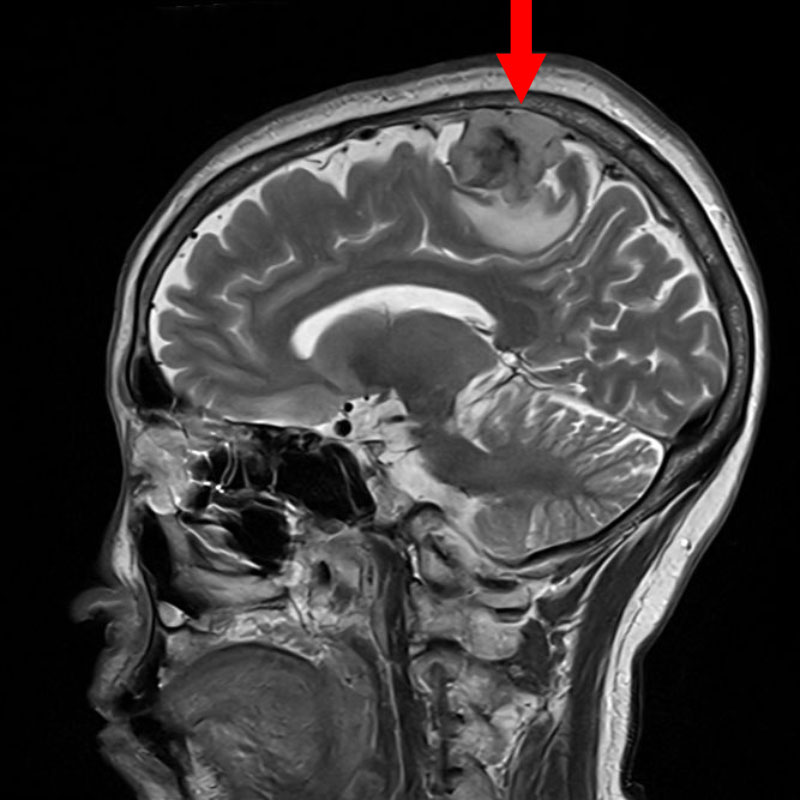

707

'25年12月

80代

髄膜腫

頭蓋内腫瘍摘出術

No.’25_109 手術前1

No.’25_109 手術前2